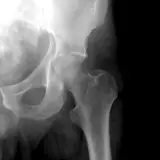

Over 2,100 interactive radiology cases, curated by radiologists for your level of training. Scroll, window, and view cases full screen — just like on PACS. Click linked findings in each writeup to jump straight to them on the image. Cases include sample reports, a focused discussion section, original illustrations, and videos.

Casos totalmente interativos com as ferramentas que você espera em um PACS — rolagem, ajuste de janela, zoom, movimentação, medidas, ROIs e modo de tela cheia.

Casos Interativos

Role, movimente, ajuste janela e amplie como em uma estação PACS do trabalho